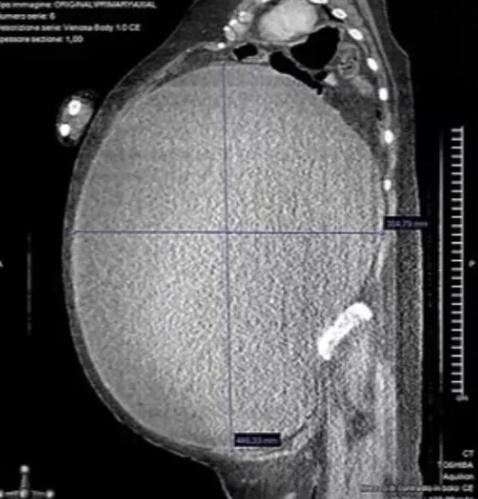

綜合報道,CT診斷發現,女子罹患邊緣性卵巢瘤(Borderline ovarian tumor,BOT),腹部完全被腫瘤佔據,醫生在進行子宮切除術前,排出了囊腫中37升的濃稠棕色液體,經過6個小時手術,才成功取出腫塊,女子期間失血6公升,手術後她住院留醫了2個月,一半時間都待在加護病房,還曾發生了心臟驟停。研究人員說,2年後,女子完全康復,沒有任何疾病。該病例報告近期發表在《美國病例報告雜誌》上。

CT診斷發現,女子罹患邊緣性卵巢瘤(Borderline ovarian tumor,BOT),腹部完全被腫瘤佔據。(網上圖片)